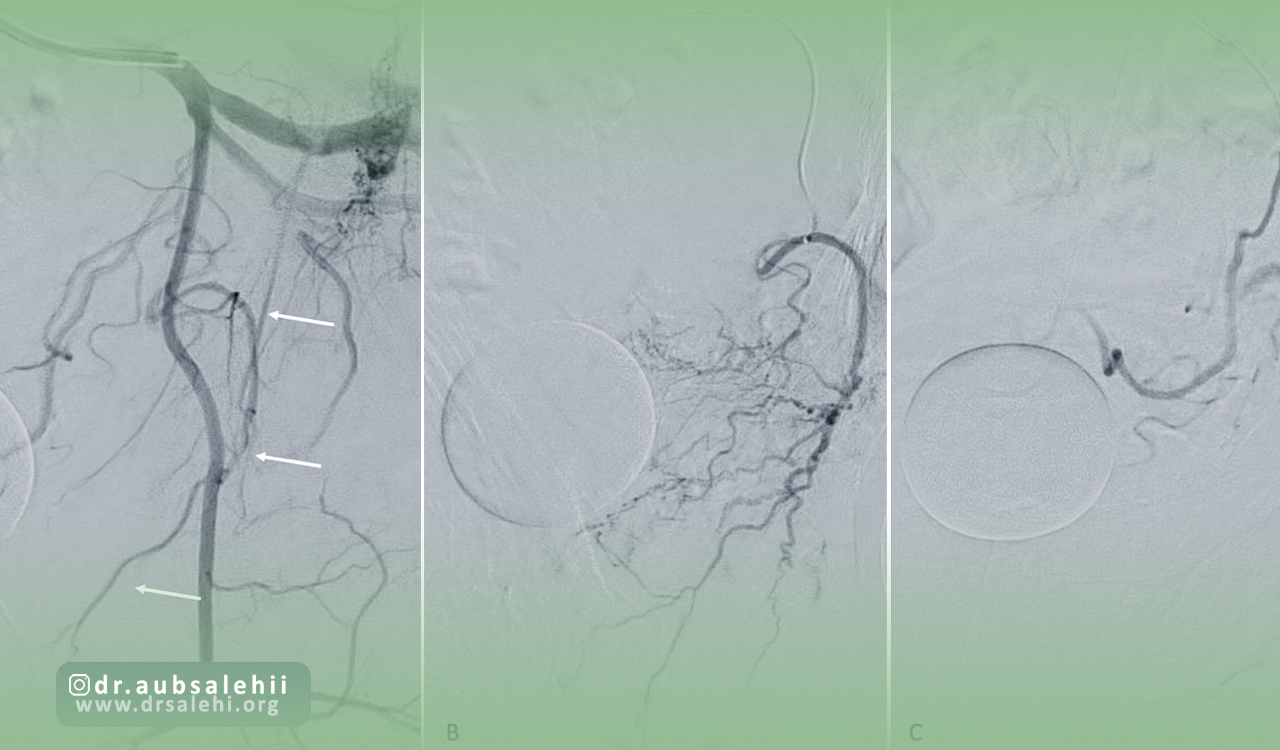

بعد از ایجاد برش در محدوده مورد نظر کاتتر که لوله نازک است وارد شریان اصلی میشود، در ادامه متخصصان ضمن تصویربرداری با اشعه ایکس کاتتر را به سمت شریان های تغذیه کننده پروستات هدایت می کنند.

بعد از رسیدن کاتتر به عروق مورد نظر ماده حاجب از طریق کاتتر تزریق شده تا پزشک بتواند شریان ها را به خوبی بررسی کند.

در مراحل پایانی مواد آمبولیزاسیون یا همان میکرو ذرات یا چسب های پزشکی از طریق کاتتر به داخل شریان های پروستات تزریق میشود تا میزان جریان خون را در این محدوده کاهش دهند و رگ ها را مسدود کنند.

بعد از انجام این کار و زمانی که پزشک از انسداد رگ های هدف مطمئن شد کاتتر را به آرامی از رگ خارج می کنند و برش ایجاد شده را به واسطه بخیه ترمیم می کنند.

آنژیوگرافی پروستات پیش از انجام آمبولیزاسیون شریان پروستات (PAE) انجام میشود تا مسیرهای عروقی و ساختارهای مهم بهطور کامل مشخص شوند.

این اطلاعات، ریسک عوارض جانبی را کاهش داده و دقت درمان را افزایش میدهد.

در این مرحله، پزشک میتواند بهترین استراتژی را برای مسدود کردن عروق غیرضروری پروستات تعیین کند.

آنژیوگرافی پروستات یک روش تصویربرداری تشخیصی است که با تزریق ماده حاجب به عروق پروستات انجام میشود تا نقشه دقیقی از خونرسانی این غده به دست آید.

این مرحله بیشتر جنبه ارزیابی دارد و کمک میکند محل و شدت جریان خون پروستات مشخص شود.

در مقابل، آمبولیزاسیون پروستات یک روش درمانی است که طی آن با استفاده از همان مسیر آنژیوگرافی، ذرات ریز مخصوصی به داخل عروق پروستات تزریق میشود تا جریان خون کاهش یابد و حجم پروستات کوچکتر شود.

این فرآیند منجر به کاهش فشار بر مجرای ادراری و بهبود علائم بیمار میگردد.

تفاوت اصلی این دو روش در هدف و کاربرد آنهاست؛ آنژیوگرافی تنها یک ابزار تشخیصی است، در حالی که آمبولیزاسیون یک مداخله درمانی محسوب میشود.

پزشک معمولاً پس از انجام آنژیوگرافی و بررسی نتایج، در صورت مناسب بودن شرایط، اقدام به آمبولیزاسیون میکند.